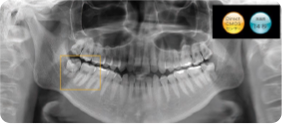

レントゲン撮影

虫歯や歯周病の根本原因をしっかり把握するために、レントゲンや唾液検査でお口まわりの現状を見える化します。